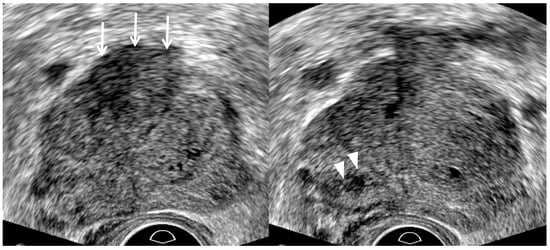

| TRUS Features | Peripheral Cancer | Transition Cancer | ||

|---|---|---|---|---|

| Insignificant Cancer | Significant Cancer | Insignificant Cancer | Significant Cancer | |

| Echogenicity | Low | Lower | High | Higher |

| Size | Small | Large | Small | Large |

| Echotexture | Homogeneous | Heterogeneous | Homogeneous | Heterogeneous |

| Margin | Smooth | Irregular | Smooth | Irregular |

| Perfusion | Low | High | NA | NA |

| Hypoechoic rim | NA | NA | Clear | Unclear |